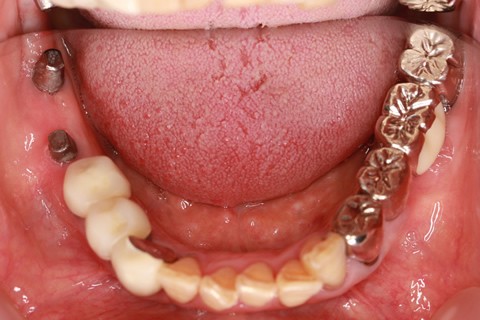

• 症例2

治療前

インプラント埋入時

治療後

年齢・性別

57歳男性

治療期間

3ヶ月

抜歯

なし

治療費

154万円

備考

左上5.6.7 及び左下6.7欠損

治療内容

左上5.6.7と左下6.7欠損部にインプラント埋入

施術の副作用(リスク)

オペによる知覚障害。インプラントによる歯肉炎。インプラント脱落。